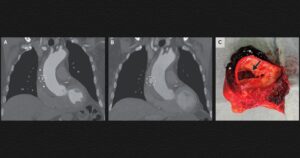

Нидерландцу удалили гематому в стенке аорты. Операция прошла успешно

В неотложное отделение нидерландской больницы поступил 80-летний мужчина без особенностей в анамнезе с жалобами на боль в грудной клетке в течение 12 часов и повышением уровня D-димера (маркера недавнего тромбоза). Его артериальное давление было 147/92 миллиметра ртутного столба, пульс — 70 ударов в минуту, а данные осмотра — нормальными. Компьютерная томографическая ангиография легких не выявила …